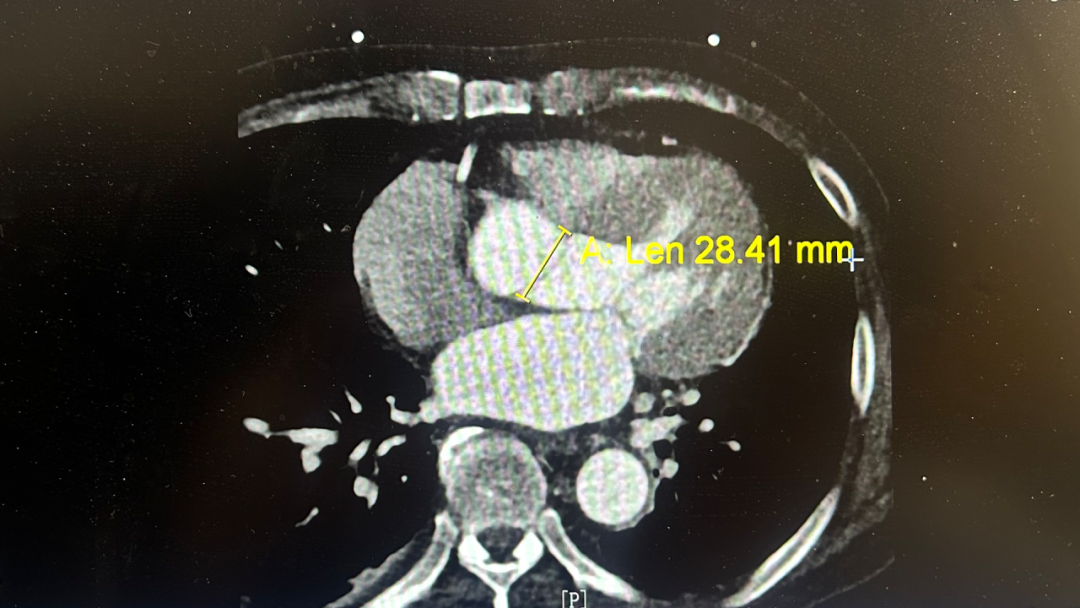

主动脉瓣环直径达28.41mm

更棘手的是,李先生的主动脉瓣环直径达28.41mm,属于超大尺寸。“瓣环越大,对人工瓣膜的尺寸要求就越高,可供选择的型号非常有限。”迟路湘教授坦言。

针对李叔叔 28.41mm 的超大瓣环,团队选择了 32mm ScienCrown 生物瓣——“这是该款瓣膜目前最大的尺寸型号,再大就没有同系列合适材料了。”